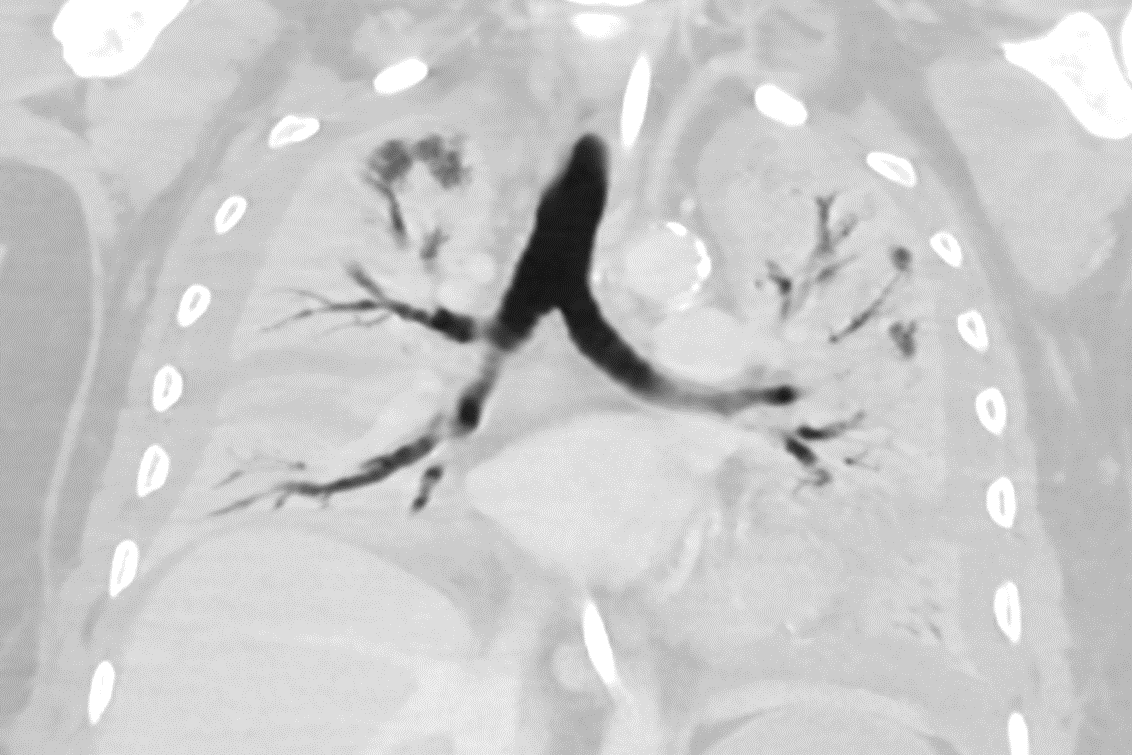

The following factors were established as criteria for potential transplantation: exhaustion of all conservative treatment options, no recovery of the Covid-19-damaged lungs despite at least four weeks of ventilation/ECMO, evidence of advanced and irreversible lung damage in several consecutive CT scans, age below 65 and no relevant comorbidities. In addition to this, candidates for a lung transplant must be in good physical condition and have a good chance of complete physical rehabilitation following the transplant. "These guidelines can be applied worldwide for making a sound selection of patients who are suitable for a lung transplant following a Covid-19 infection."